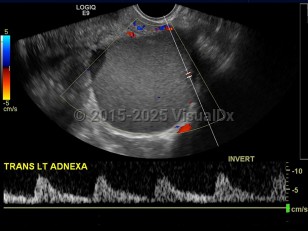

The endometrium is the innermost lining layer of the uterus. Its function is to stabilize and support an early pregnancy. When fragments of endometrial lining are found outside of the uterine cavity, this is referred to as endometriosis.

The exact etiology of this condition is unclear, but the prevailing thoughts are toward retrograde menstruation (endometrial fragments pushed into the abdomen through the fallopian tubes) and localized lymphatic spread. Areas affected can include all abdominal organs but most commonly involve the ovaries, bladder, fallopian tubes, and the uterine support ligaments. Less common sites of involvement may include the umbilicus, incisional scars, and the omentum.

Each month, due to hormone effects, lesions cycle through changes that ultimately lead to scar tissue and adhesions. This cycling process and scarification cause chronic inflammation and pain.